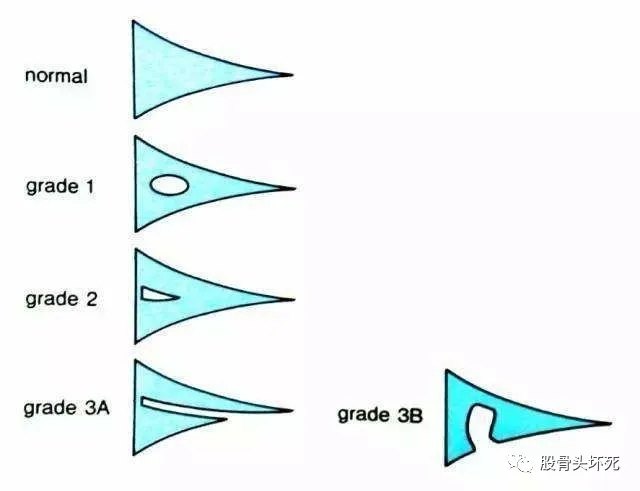

半月板因其是软骨,常规X线与CT无法显示其形态,故损伤多由核磁(MRI)确诊。那么报告单上的Ⅰ、Ⅱ、Ⅲ度是什么意思呢?首先,Ⅰ度损伤是指MRI上半月板内出现较小的局灶性(椭)圆形高信号灶,不与关节面接触,是最轻度的半月板损伤;Ⅱ度只是半月板内线形高信号,与关节面仍无接触,损伤程度较Ⅰ度重;Ⅲ度损伤是指半月板内线形或不规则高信号接触一/两个关节面,是事实上的完全撕裂。